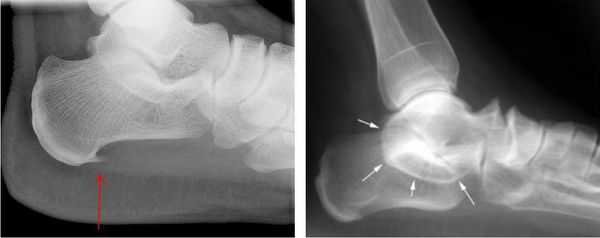

Рис 2. Иррадиация болевых ощущений при наличии синдрома тарзального канала.

Визуально определяемые атрофические изменения мышечных тканей стопы, как и когтеобразная деформация пальцев, могут говорить о хроническом сдавливании нерва.

При этом, рентгенографические исследования (МРТ, КТ, УЗИ) стопных отделов под нагрузкой, позволяют выявить наличие/отсутствие различных деформационных изменений, остеофитов, переломов, а также иных видов проблем, провоцирующих изменение нормальной формы канала предплюсны.

Как правило, рентген помогает специалисту получить оптимально корректную информацию и, на ее основе, применить наиболее эффективную тактику лечения - консервативную, либо хирургическую.

Рис 3. МР-признаки наличия жидкостного ганглия, оказывающего патологическое давление на большеберцовый нерв.